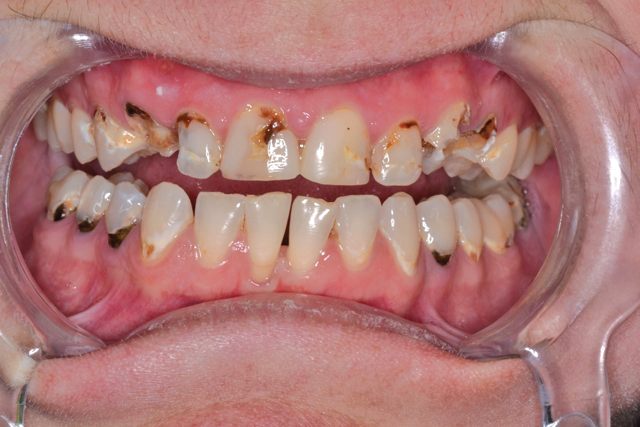

Sally suffered from years of neglect, trauma and abuse. Her teeth were a disaster, but her life was turning around, and she wanted to save her smile and regain her self-confidence (Fig. 1).

Fig. 1 Fig. 2

Sally started soft-tissue therapy while I worked with my lab to create an idealized diagnostic wax-up and refractory putty matrix (Fig. 2). At her pre-op hygiene visit, she presented with healthy tissue, and upon seeing the smile design wax-up, she was quite emotional.